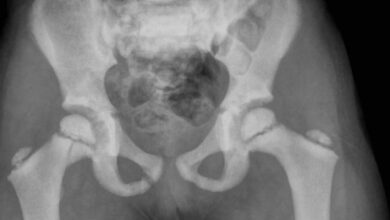

- كسر بسهولة في العظام مع القليل من الصدمات على مدى العمر. (غالبًا ما توجد العظام المكسورة عند الولادة ، وقد تكشف الأشعة السينية عن كسور عظام ملتئمة حدثت قبل الولادة).

- طلب فحوصات الأشعة السينية وكثافة العظام.